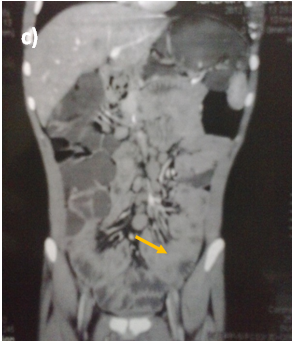

Abdominal ultrasound showed uniform circumferential mural thickening of the small bowel loops, so we proceeded to C.T Enterography. As shown in Figure 1, there is diffuse uniform thickening of the small bowel loops mainly involving the ileum with no focal thickening or masses. Then upper endoscopy and colonoscopy were performed to the patient and they showed multiple tiny rounded nodules at the terminal ileum that were biopsied and revealed non-specific inflammation free of granuloma or malignancy. Then we proceeded to double balloon enteroscopy which was done by an over tube double balloon Fuji series endoscopy, which proceeded to about 200cm from the duodenal bulb. Double balloon endoscopy as shown in Figure 2, showed numerous visible mucosal nodules measuring few millimeters in diameter involving the whole part of the small intestine examined which were biopsied. Histopathology revealed chronic inflammatory enteritis with foci of lymphoid aggregates with no atypia or malignancy (Table 1).

Figure 1 C.T. Enterography of the patient that showed diffuse uniform thickening of the small bowel loops mainly involving the ileum with no focal thickening or masses.